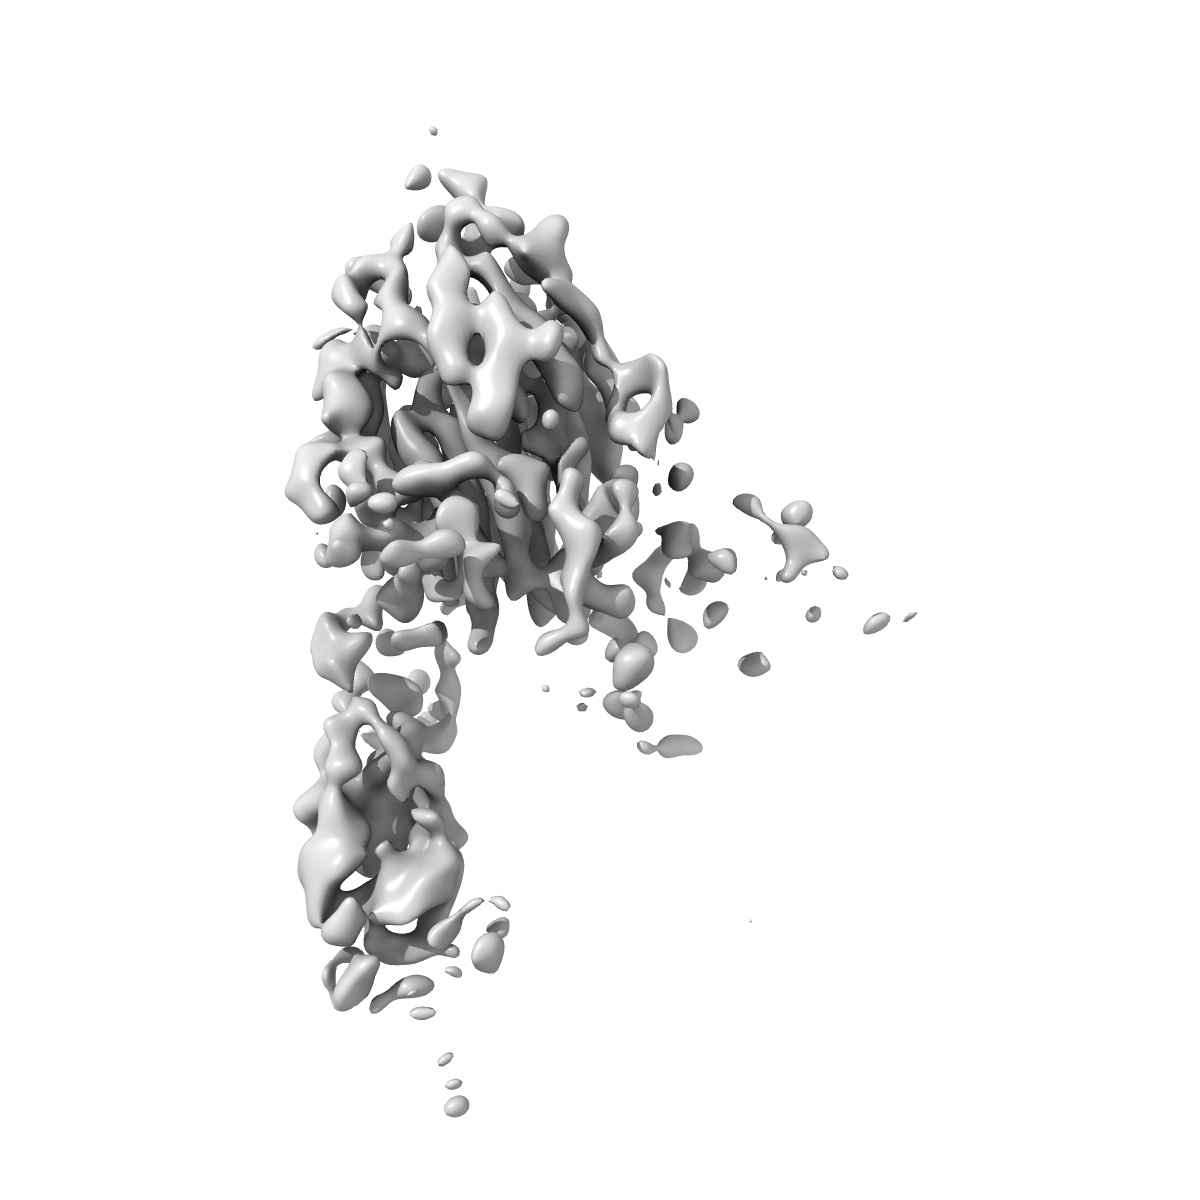

Structure of the SARS-CoV-2 spike trimer in complex with mRNA vaccine induced neutralizing antibody C663

Single-particle5.0 Å

Sample: SARS-CoV-2 S 6P trimer complexed with monoclonal Fab C601